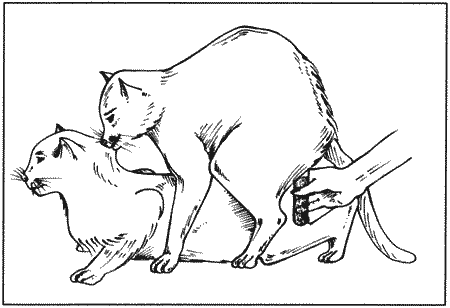

Вагинальная эндоскопия

Прекращение секреции эстрадиола фолликулами и переход их к секреции прогестерона приводят к снижению как отечности, так и васкуляризации слизистых оболочек, что сопровождается выраженным изменением характера вагинальных выделений, выявляемым с помощью вагинальной эндоскопии. На стадии проэструса слизистая оболочка становится более выпуклой и отечной, затем наблюдается ее уменьшение; по мере приближения овуляторного пика слизистая сжимается и бледнеет, в некоторых случаях становясь практически белой (фиг. 1.1). Перечисленные изменения свидетельствуют о приближении стадии, характеризующейся постепенным повышением концентрации прогестерона перед овуляцией и последующим наступлением фертильного периода. Эти изменения легко узнать, имея даже небольшую практику (фиг. 1.3), кроме того, они настолько воспроизводимы, что по набору признаков их можно оценивать полуколичественно. Вагинальная эндоскопия весьма полезна в определении оптимальных сроков вязки. По окончании фертильного периода, т. е. в начале метэструса — слизистая оболочка влагалища бледнеет и истончается, складки становятся закругленными — и что, вероятно, является наиболее характерным признаком, — слизистая в переднем отделе влагалища выглядит раздраженной и при прикосновении быстро сжимается, образуя розетку.

Фиг. 1.3.

Эндоскопическое исследование слизистой влагалища. Динамика изменений на протяжении цикла: (а) проэтрус — розовая окраска и отечность; (b) начало эструса — слизистая бледнеет, отек начинает уменьшаться (обычно перед пиком ЛГ); (c) середина эструса — слизистая бледная, уменьшение отека (сморщивание) явно выражено, что соответствует середине фертильного периода; (d) начало метэструса — видны закругленные складки, при прикосновении слизистая смыкается, образуя розетку (е) (см. Приложение)